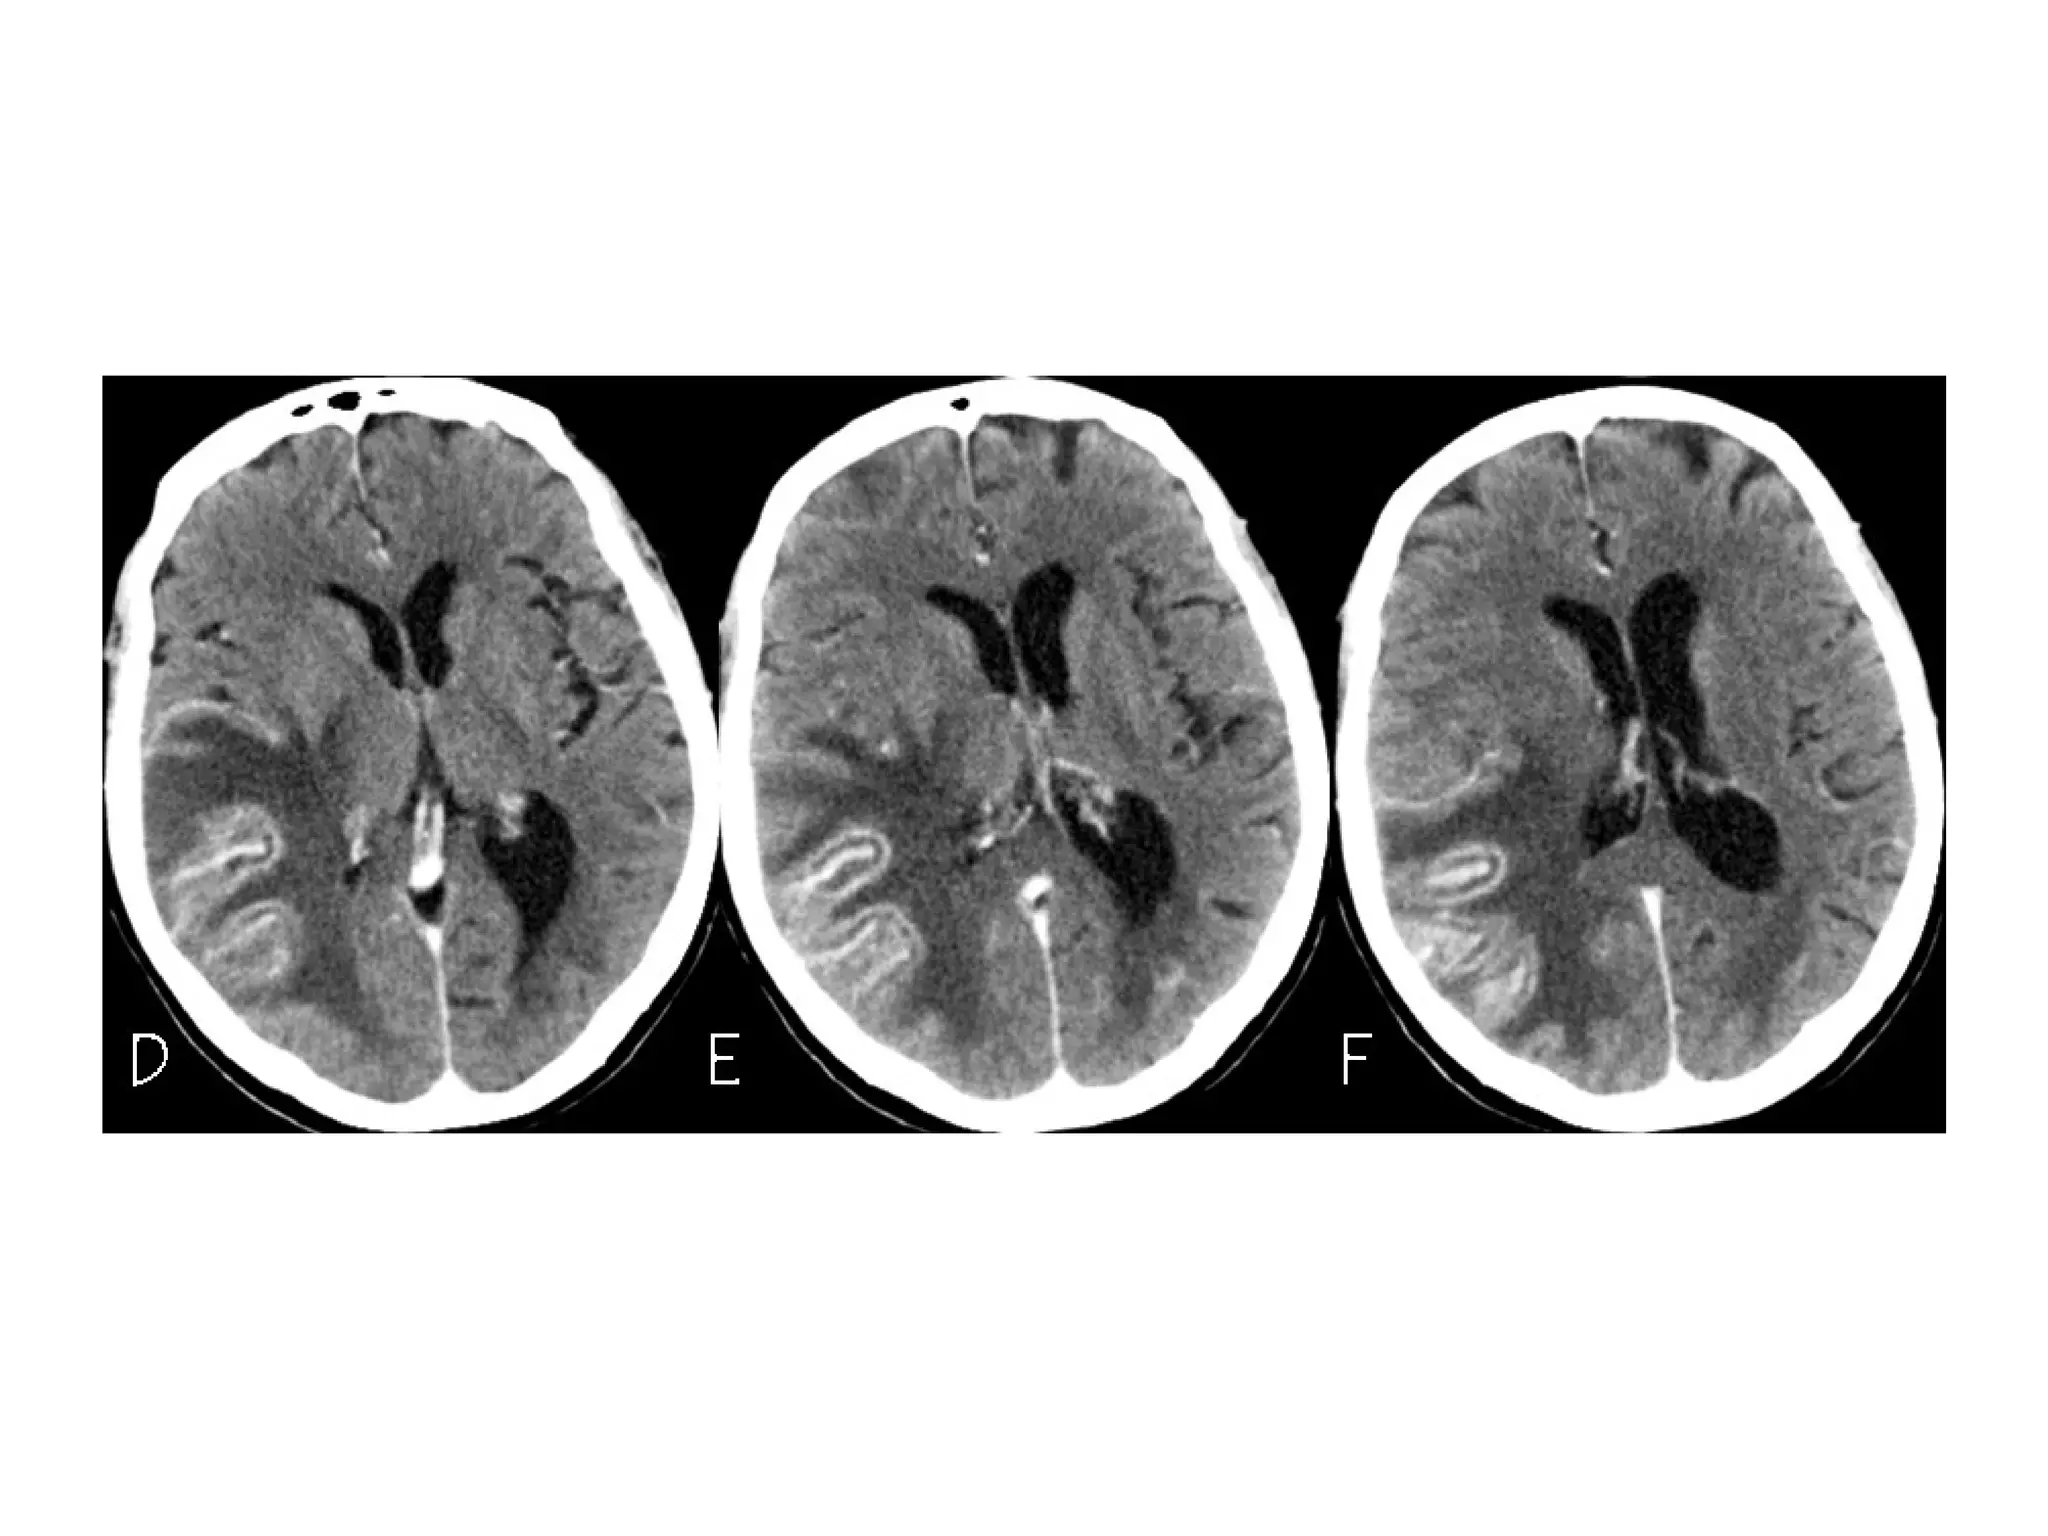

Patient with deep cerebral vein thrombosis , notice the bilateral infarctions in

the basal ganglia

The same patient , there is absence of flow void in the internal

cerebral veins, straight sinus and right transverse sinus (blue

arrows) , on the MRA the right transverse sinus is not visualized